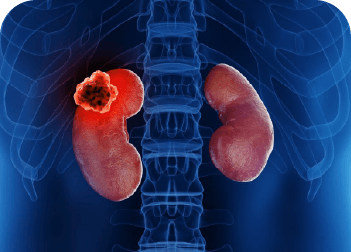

Tumor de Riñon

Crecimiento anormal de células en el riñón, que puede ser benigno o maligno.

Nefroctomía simple y radical

Cirugía para retirar parcial o totalmente un riñón, indicada en casos de tumores, enfermedades graves o daño irreversible del órgano.

Destechamiento de quiste renal laparoscópico

Cirugía mínimamente invasiva para tratar quistes renales grandes o sintomáticos mediante pequeñas incisiones y técnicas laparoscópicas.